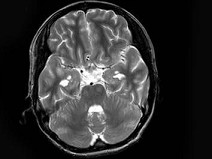

男,17岁,头痛呕吐,发热20天,脑膜刺激征阳性,MRI平扫及增强扫描,最可能的诊断是()

• A.结核性脑膜脑炎

• B.化脓性脑膜脑炎

• C.寄生虫感染

• D.颅内转移瘤